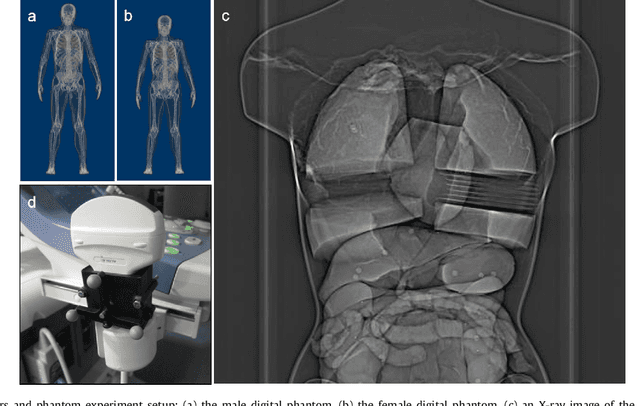

Abstract:Robot-assisted Fenestrated Endovascular Aortic Repair (FEVAR) is currently navigated by 2D fluoroscopy which is insufficiently informative. Previously, a semi-automatic 3D shape instantiation method was developed to instantiate the 3D shape of a main, deployed, and fenestrated stent graft from a single fluoroscopy projection in real-time, which could help 3D FEVAR navigation and robotic path planning. This proposed semi-automatic method was based on the Robust Perspective-5-Point (RP5P) method, graft gap interpolation and semi-automatic multiple-class marker center determination. In this paper, an automatic 3D shape instantiation could be achieved by automatic multiple-class marker segmentation and hence automatic multiple-class marker center determination. Firstly, the markers were designed into five different shapes. Then, Equally-weighted Focal U-Net was proposed to segment the fluoroscopy projections of customized markers into five classes and hence to determine the marker centers. The proposed Equally-weighted Focal U-Net utilized U-Net as the network architecture, equally-weighted loss function for initial marker segmentation, and then equally-weighted focal loss function for improving the initial marker segmentation. This proposed network outperformed traditional Weighted U-Net on the class-imbalance segmentation in this paper with reducing one hyper-parameter - the weight. An overall mean Intersection over Union (mIoU) of 0.6943 was achieved on 78 testing images, where 81.01% markers were segmented with a center position error <1.6mm. Comparable accuracy of 3D shape instantiation was also achieved and stated. The data, trained models and TensorFlow codes are available on-line.

Abstract:Robot-assisted deployment of fenestrated stent grafts in Fenestrated Endovascular Aortic Repair (FEVAR) requires accurate geometrical alignment. Currently, this process is guided by 2D fluoroscopy, which is uninformative and error prone. In this paper, a real-time framework is proposed to instantiate the 3D shape of a fenestrated stent graft based on only a single low-dose 2D fluoroscopic image. Firstly, the fenestrated stent graft was placed with markers. Secondly, the 3D pose of each stent segment was instantiated by the RPnP (Robust Perspective-n-Point) method. Thirdly, the 3D shape of the whole stent graft was instantiated via graft gap interpolation. Focal-Unet was proposed to segment the markers from 2D fluoroscopic images to achieve semi-automatic marker detection. The proposed framework was validated on five patient-specific 3D printed phantoms of aortic aneurysms and three stent grafts with new marker placements, showing an average distance error of 1-3mm and an average angle error of 4 degree.